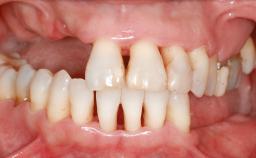

An 80-year-old female patient was referred to clinic for rehabilitation of her dentition. The patient’s medical history revealed no significant findings that would preclude routine dental and oral surgical procedures. She reported no drug allergies and was currently taking no prescription medications.

Her chief complaint was her inability to masticate efficiently due to the recent loss of her mandibular second premolars and first molars bilaterally. She expressed a desire for fixed prostheses in the shortest possible time due to her advanced age, requesting that replacement teeth should look as natural as possible. She was otherwise comfortable and not experiencing any symptoms from her teeth.